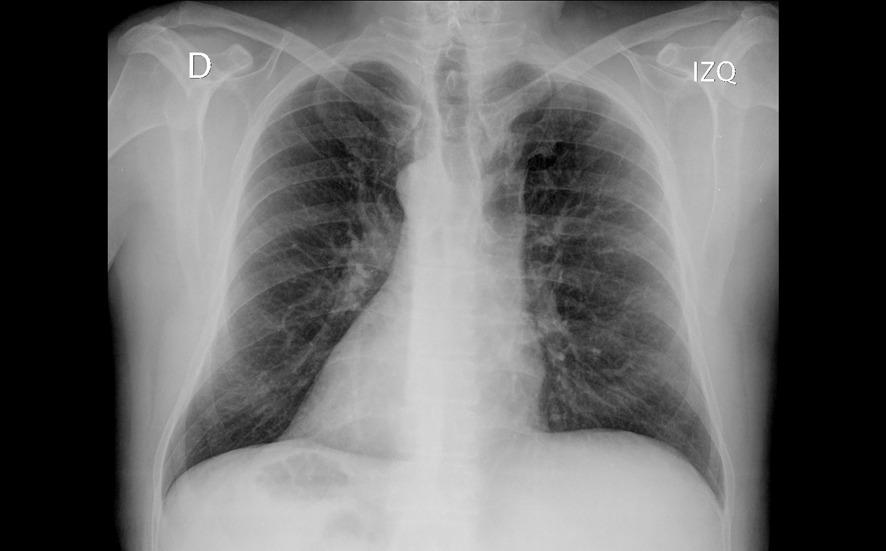

El paciente presentó mejoría rápida del dolor torácico tras analgesia, permaneciendo hemodinámicamente estable y sin nueva sintomatología. Los exámenes de laboratorio y la radiografía de tórax no mostraron alteraciones. La ecografía torácica/abdominal evidenció un situs inversus total como hallazgo incidental, sin relación con el cuadro clínico. Durante la observación evoluciona asintomático, con adecuada ventilación y sin dolor, por lo que se decide alta con educación respecto a su condición anatómica y recomendaciones para seguimiento.

La integración de un examen físico completo, en conjunto con los hallazgos característicos del electrocardiograma y la confirmación estructural mediante ecocardiograma, permite establecer con precisión el diagnóstico de situs inversus. El examen físico orienta desde los primeros momentos al identificar la posición anómala de los ruidos cardíacos y, el electrocardiograma aporta patrones eléctricos sugestivos de inversión anatómica. Finalmente, el ecocardiograma y Rx confirman la disposición especular de las estructuras torácicas y cardíacas.